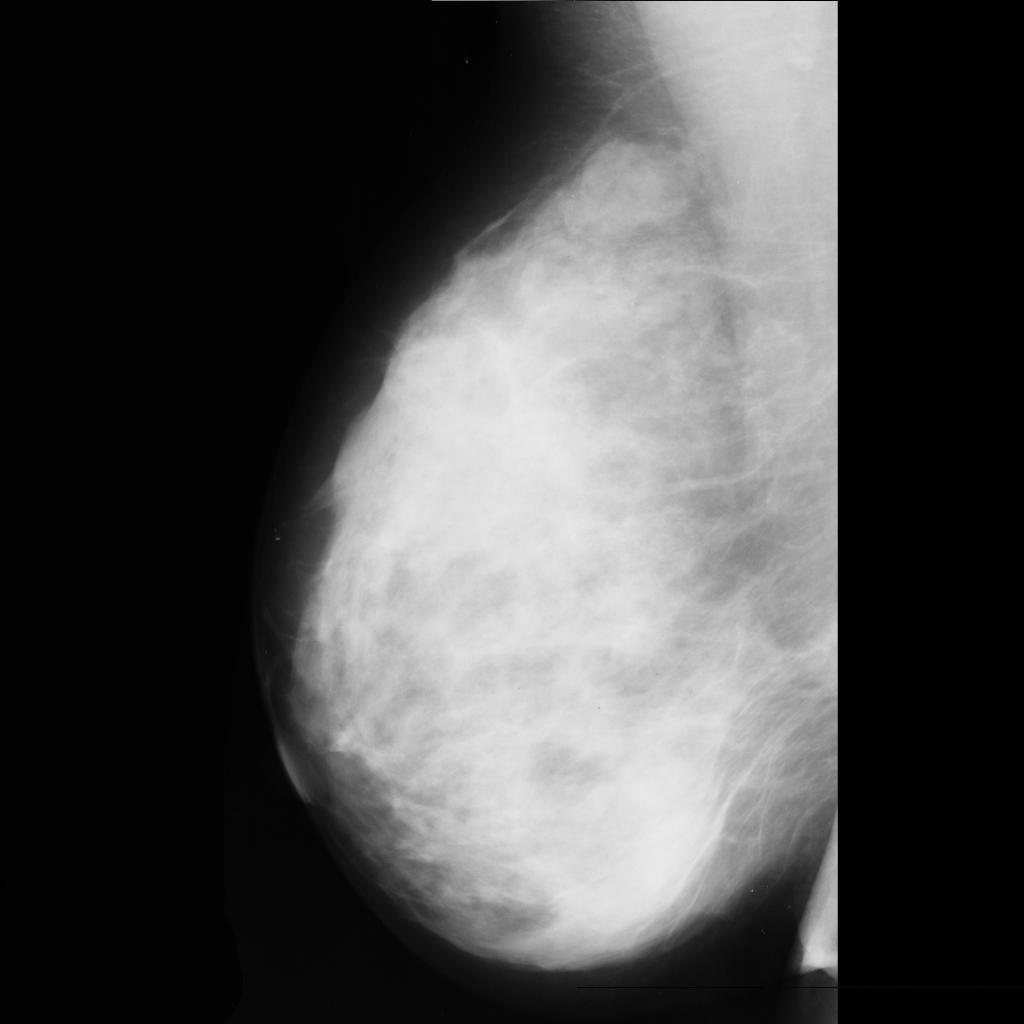

malignant